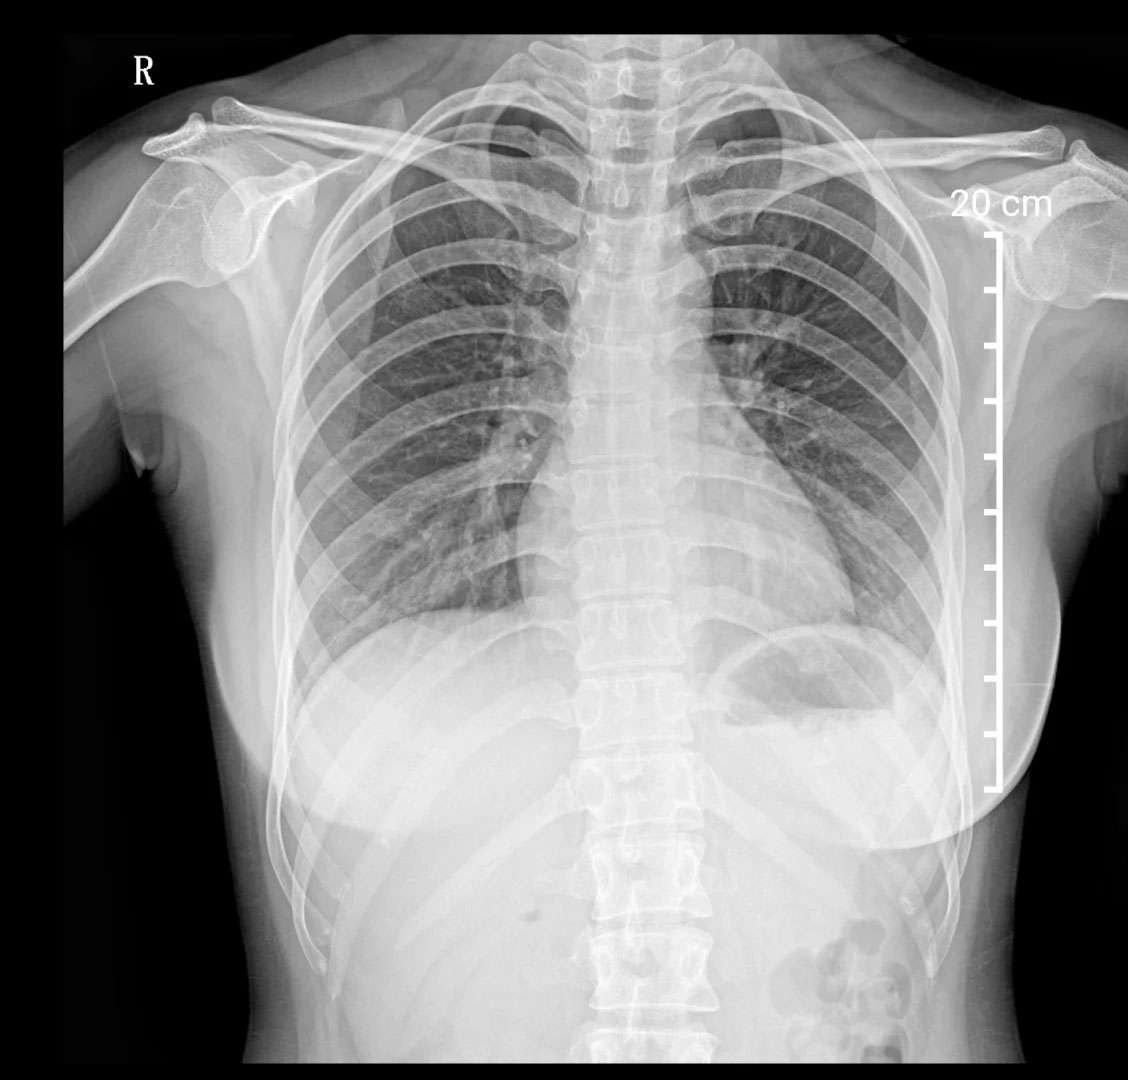

胸部X光檢查,建筑工地的環(huán)境復(fù)雜,肺部檢查很重要。有的工種需要長期接觸灰塵,可能會引起輕微肺部炎癥。在工地工作的時候,盡量要佩戴好口罩。